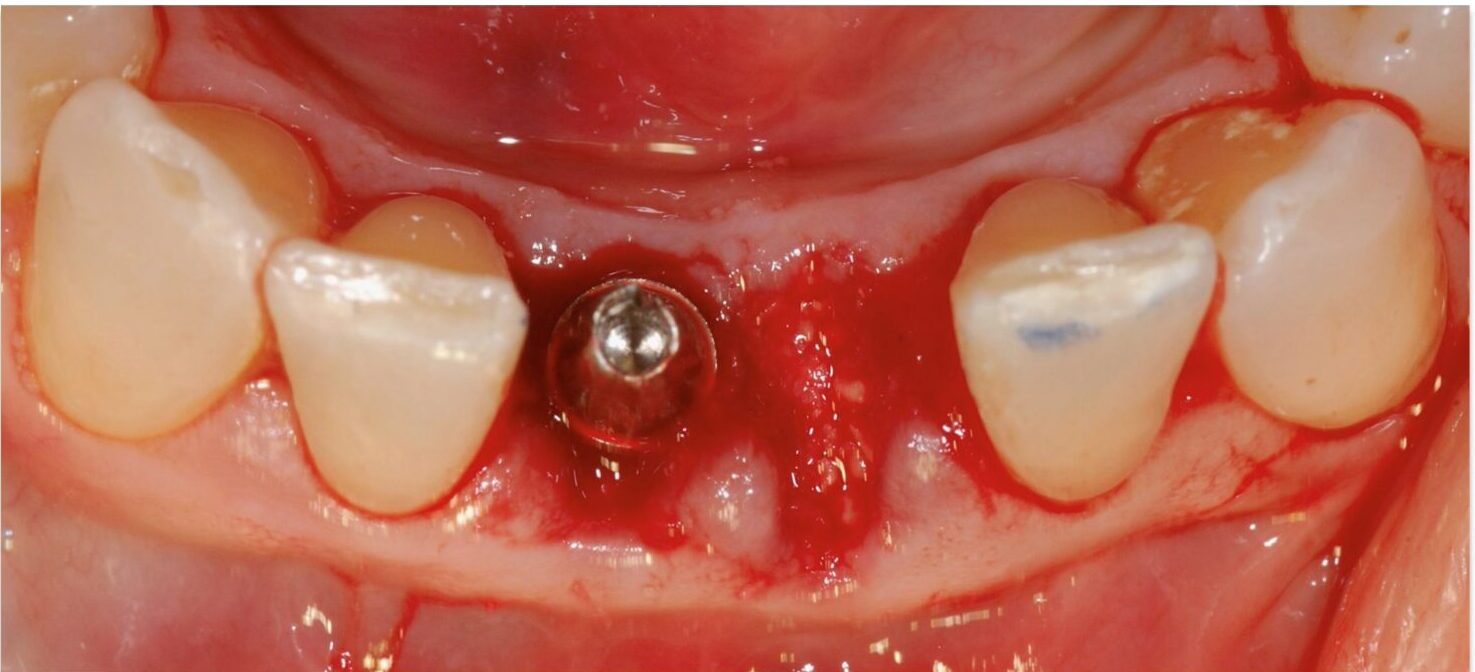

• TERAPIA IMPLANTARE DEI SETTORI ANTERIORI

• PROTOCOLLI CHIRURGICI NELL’ INSERIMENTO

DELL’ IMPIANTO POST ESTRATTIVO IMMEDIATO E

DIFFERITO A MEDIO E LUNGO TERMINE